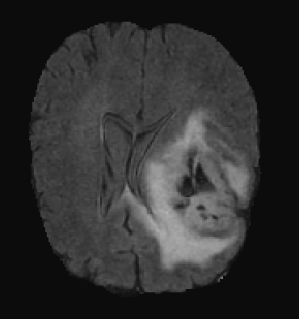

Figure 5 shows two subjects among the quantitatively better (first row) and poorer (second row) results. In both cases, it can be visually appreciated that our method correctly segments the whole tumor region. For the subject shown in Figure 5.a, the system is able to properly capture all tumor regions, meaning that the first network is able to correctly localize the tumor and the second network is able to capture differences between tumor regions. On the other hand, in Figure 5.b, we show a case where even though the tumor is correctly localized by the first network, the second isn’t able to properly detect different tumor subregions. We see that edema (ED - label 2) is overrepresented in our segmentation in detriment of smaller classes: GD-enhancing tumor (ET - label 4) and the necrotic and non-enhancing tumor (NCR/NET - label 1). This effect can also be inferred from lower values in ET and TC dice coefficients.